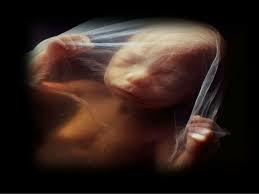

• A partir del 2º mes.

Comienza el periodo fetal.

• 2º mes. Desarrollo embrionario.

2º mes. Desarrollo embrionario.

En este periodo de tiempo, tiene lugar el desarrollo del disco germinativo, el desarrollo de los órganos y la diferenciación de células.